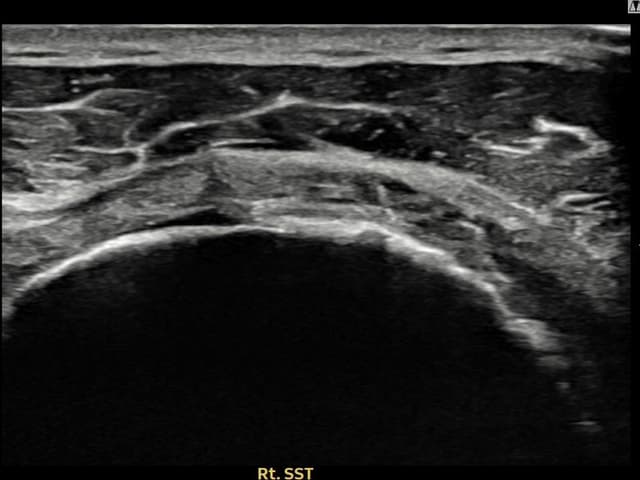

右侧 冈上肌腱 石灰化肌腱炎

14mm × 10mm